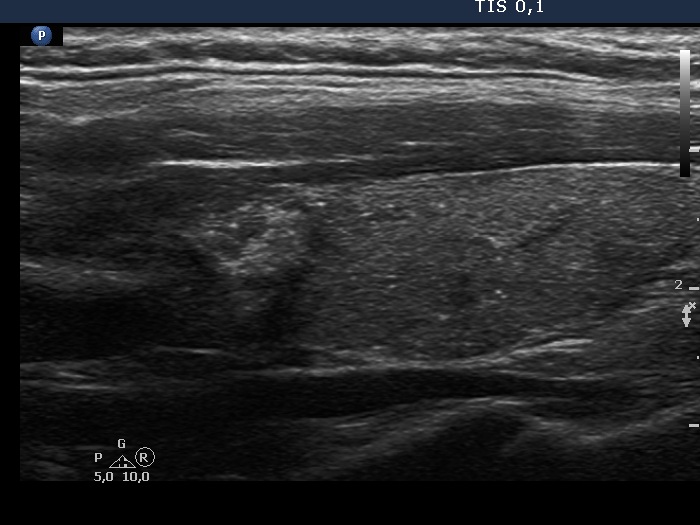

Lymph nodes - case conp 080 (ultrasonographic picture 8)

Left lobe, another longitudinal scan.